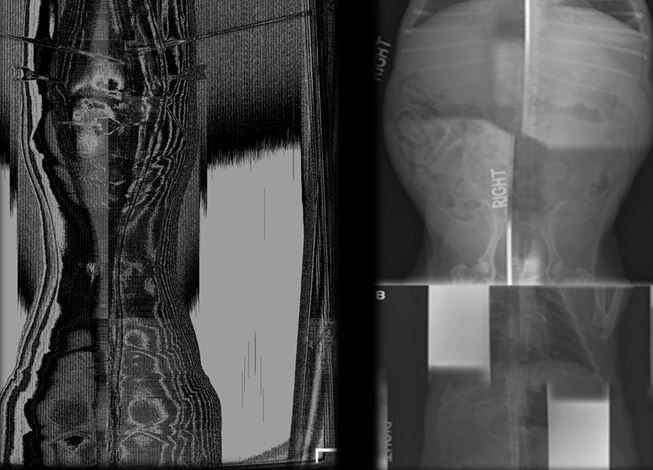

6

Q

Artifact? Fix?

A

There are two rads in that image… one with the glove is the artifact and the one without it is normal.

Density threshold - metal object change the gray-scale to exclude your wanted anatomy .

Remove metal object